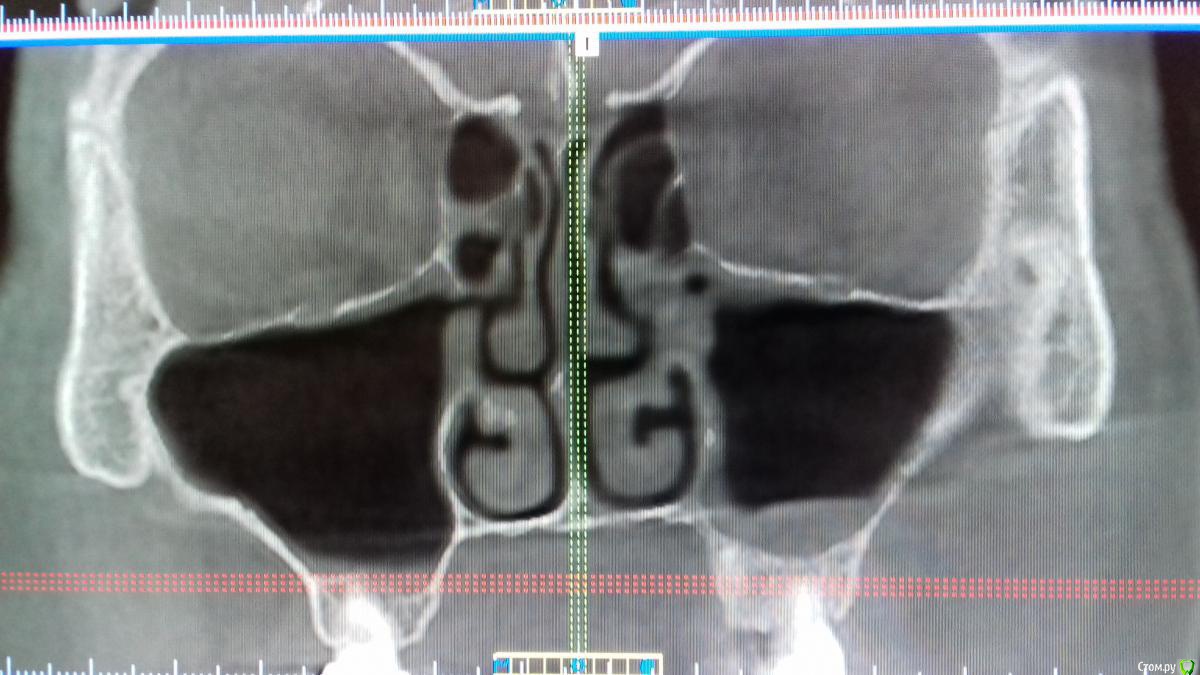

Хью Крейн Опубликовано 4 июня, 2018 Поделиться Опубликовано 4 июня, 2018 Уважаемые коллеги,нужен совет. Изначально план операции был таков:удаление корня 2.2,резекция верхушки корня 2.1, открытый синуслифтинг в области отсутствующего 2.5,вертикальная аугментация в области 2.3,2.4,2.5,консервация лунки 2.2. Закрытый остиум ставит в тупик. Пациент-курильщик. Недавно перенесено респираторное заболевание. 3.3 удален около 3 мес. назад по поводу локального парадонтального очага. Симптомов синусита не наблюдалось. К ЛОРу бы направить,но грамотного нет на примете. Ссылка на комментарий